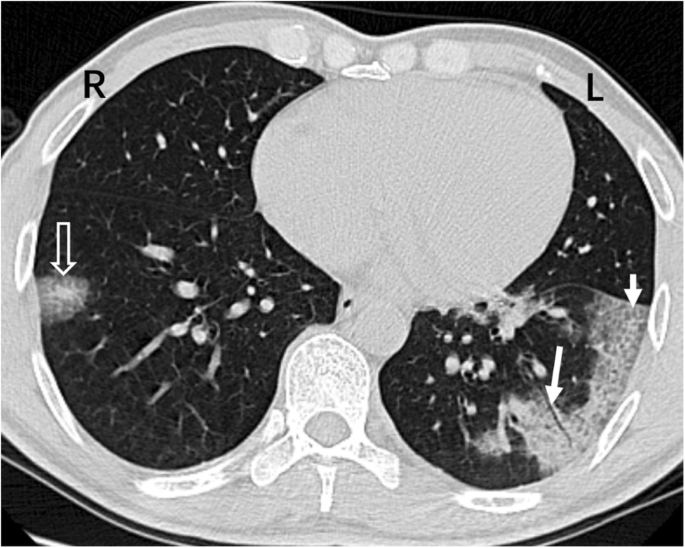

This CT image refers to the same patient (F, 39Y) as Figure 3. Patchy GGO is seen in the posterior basal segment of the left lower lobe and the posterior basal segment of the right lower lobe. The right lung lesions are localized in the peripheral lung field adjacent to the subpleural region (short white arrow). The outermost edge of the left lung lesions is 3.7 mm from the subpleural areas, and there are visible air-filled bronchi (long white arrow) inside the lesion; the white arrowheads show that a vein in the lower left lung has penetrated the lesion. R = Right, L = Left

Lesions tended to be distributed in the peripheral lung field (73.8%) (Table 2) but were seldom distributed in the central lung field (9.0%). In both groups 1 and 2, patients with involvement of the central zone were few (4 of 51 and 2 of 29 patients in groups 1 and 2, respectively), while many patients showed affected peripheral zone (21 of 51 and 25 of 29 patients in groups 1 and 2, respectively). In the peripheral zone, many lesions were adjacent to the subpleural region (284 of 548 peripheral lung lesions, accounting for 51.8%) (Figs. 2, 3, 4 and 5). In the whole lung field, the near-subpleural lesions accounted for 38.2% (284 of 743 lesions). Furthermore, the number of patients with subpleural involvement was relatively large (28 of 51 and 13 of 29 patients in groups 1 and 2, respectively).